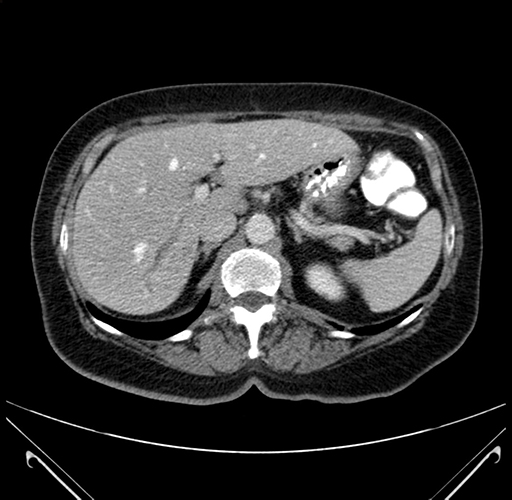

Axial Venous

Imaging analysis

Based on your CT findings, which issue(s) would give reason for "planned slowing down moment(s)" in this case?

Considering a standard right hepatectomy procedure, what step(s) of the operation would you do differently in this case?